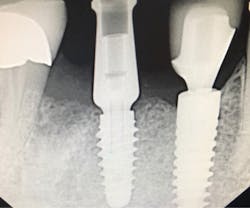

Another reason immediate placement is advantageous is that once the extraction is complete, the hole is usually already in the proper place for the implant. You may have to redirect your osteotomy slightly palatally, mesially, or distally, but the socket serves as an excellent guide for placement. In some cases, especially premolars, you can use an implant with aggressive threads to place without any osteotomy at all. You can engage the mesial and distal walls to achieve primary stability. This greatly shortens the appointment time, lowers risk, and increases patient satisfaction. Figures 1 and 2 show a MorsTorq in site No. 21 that was placed after an atraumatic extraction during my most recent two-day Louisiana Implant Institute course. Note the sharp threading on the MorsTorq, which allows for optimized immediate placement performance.There are some circumstances where immediate placement is not desirable. If the socket is too large to engage the mesial and distal walls and vital anatomical structures are located just apical to the socket, immediate placement is not recommended. Chronically infected sites also present a higher risk for immediate placement. If you can completely rid the socket of all soft tissue and the patient has the appropriate antibiotics onboard, it is possible. However, most of these cases are more predictably treated with early placement (waiting four to six weeks without grafting) or delayed placement (three to six months with grafting).